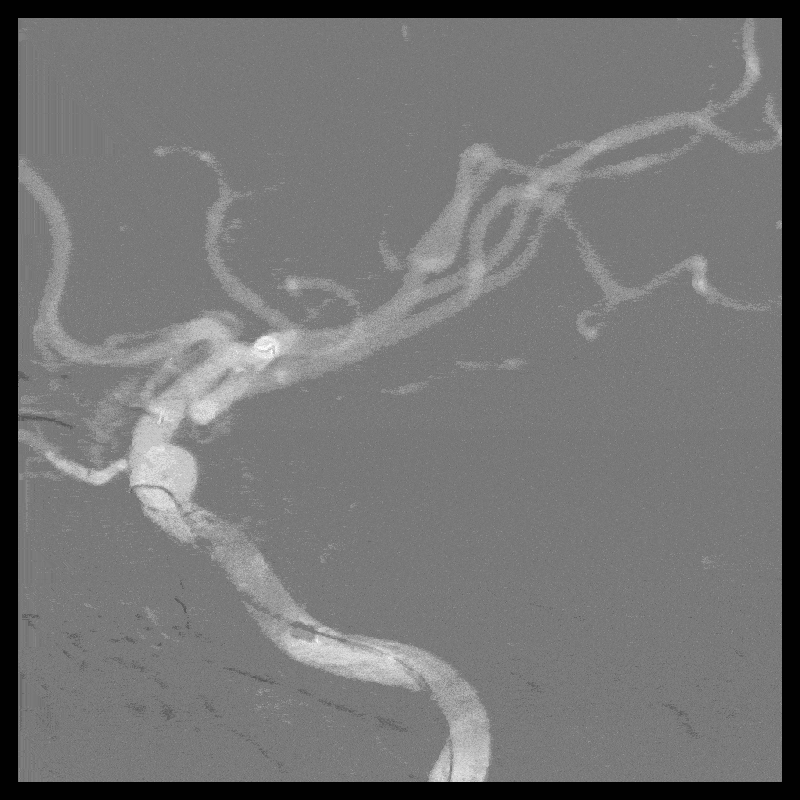

2022-2-21 右侧颈内动脉血流导向装置重建术(Tubridge)

8F Guiding+5F Navien+FasTrack

R-ICA血流导向装置(Tubridge3.5*20mm)

术后当日病情

术中10:00肝素化30mg。

10:30 手术结束。

10:50 麻醉清醒,返回病房,替罗非班1.0ml/h。